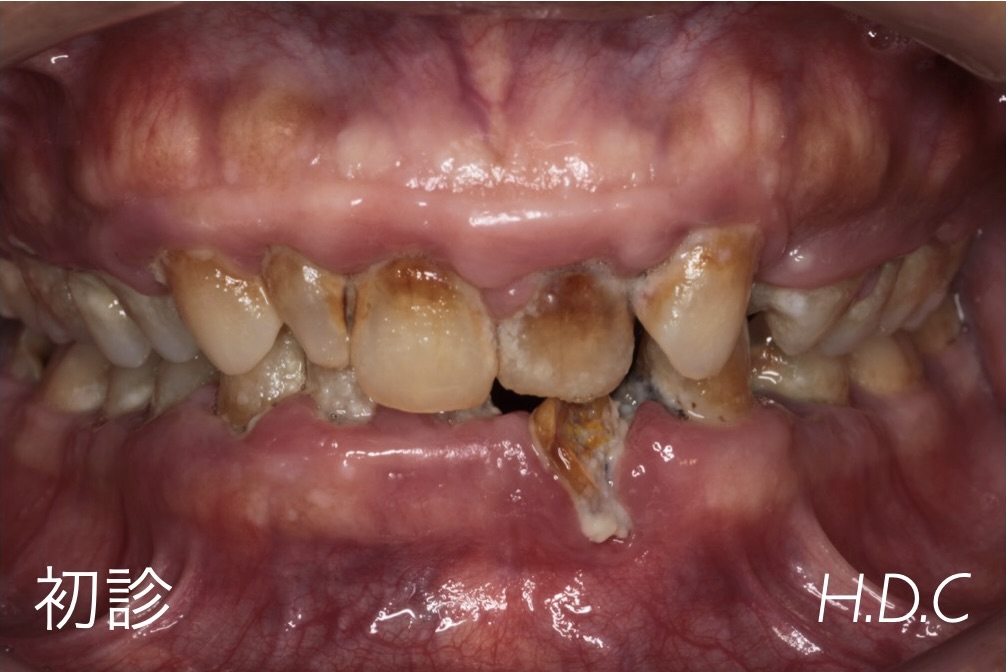

歯周病治療例⑨

(歯周基本治療症例)

- 年齢・性別

- 50代 男性

- 主訴

- 歯が欠けたので診てほしい。

- 診断名

- 重度歯周病(広汎型慢性歯周炎 Stage Ⅲ Grade B)

- 治療内容

- 歯科衛生士による歯周基本治療(ブラッシング指導、スケーリング、SRPなど)後、予後不良な歯の抜歯や、根管治療、虫歯治療、欠損補綴(ブリッジ)を行いました。

- 治療期間

- 約1年半

- 治療費用

- すべて保険診療

- リスク

- 知覚過敏、歯肉退縮、歯周病の再発など